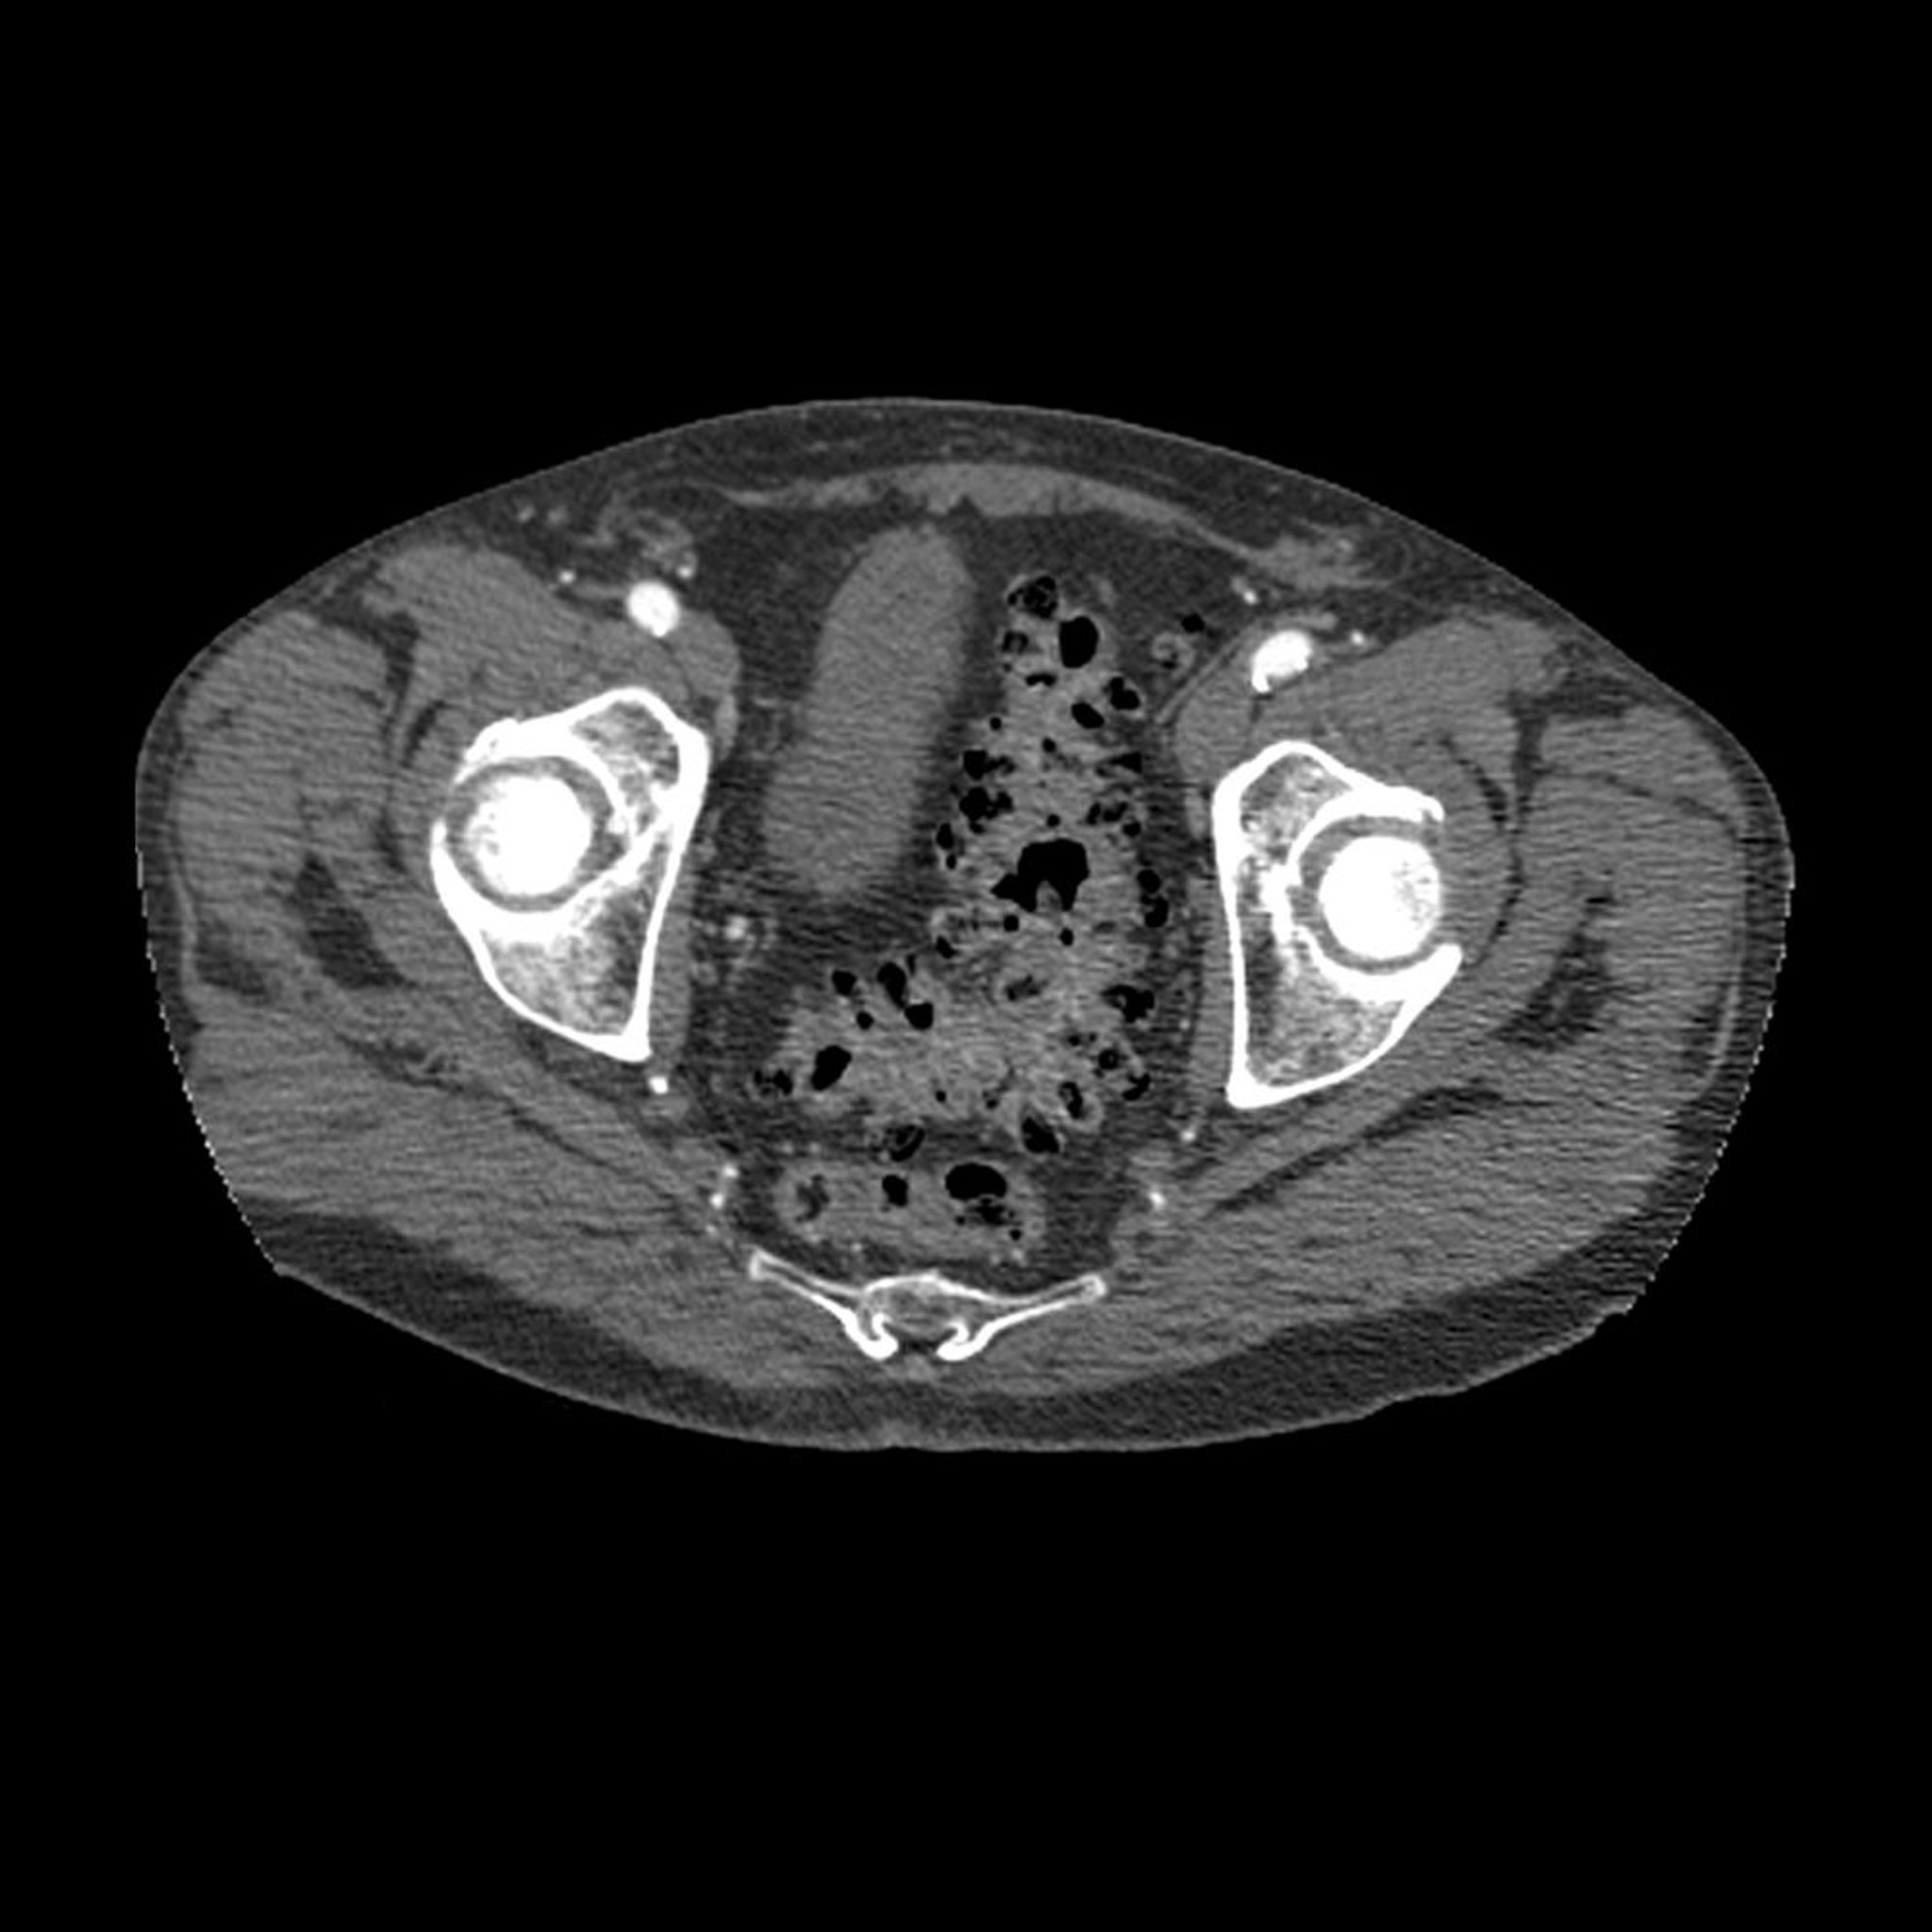

На этом осевом КТ-изображении таза в поперечном сечении показано типичное проявление дивертикулеза (темные участки стенки сигмовидной кишки).